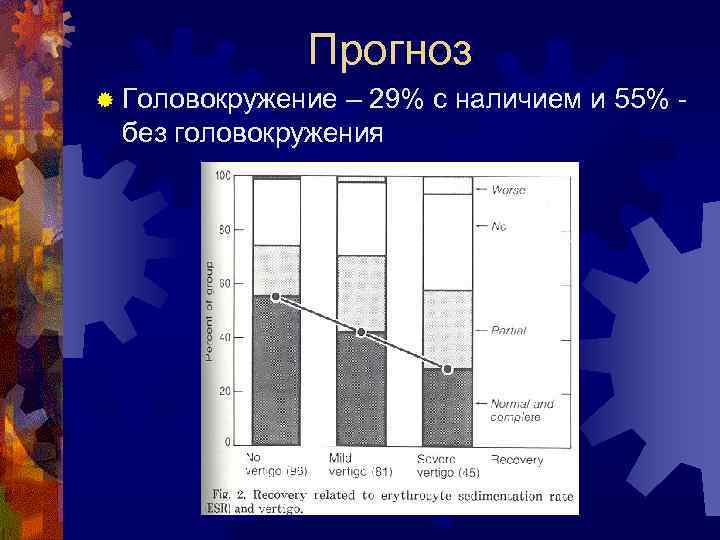

Прогноз ® Головокружение – 29% с наличием и 55% - без головокружения